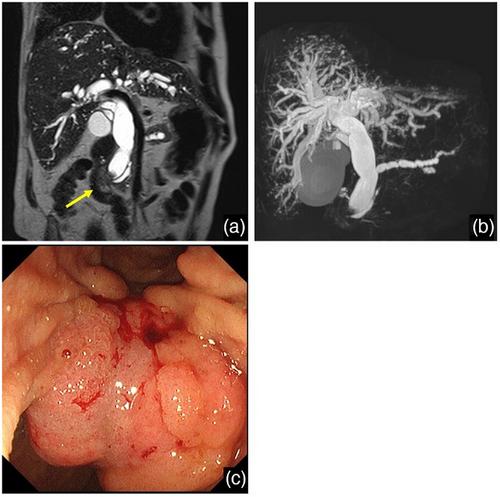

{"title":"超声内镜引导下肝胃造口术后危及生命的肝动脉假性动脉瘤破裂:急诊经导管动脉栓塞成功处理","authors":"Hiroshi Yukimoto,&nbsp;Akino Okamoto,&nbsp;Kohsaku Ohnishi,&nbsp;Keitaro Masuko,&nbsp;Junping Wang,&nbsp;Kazuya Ogawa,&nbsp;Ken Ueda,&nbsp;Motohiro Hirao,&nbsp;Yasuhiro Nakaya,&nbsp;Atsushi Hosui","doi":"10.1002/deo2.70176","DOIUrl":null,"url":null,"abstract":"<p>A 70-year-old male with lung cancer and interstitial pneumonia was diagnosed with ampullary carcinoma, causing obstructive jaundice. After the failure of endoscopic retrograde cholangiopancreatography, endoscopic ultrasound-guided hepaticogastrostomy (EUS-HGS) was performed with a 7-Fr plastic stent (PS) into the B2 bile duct. Three months later, mild bleeding was observed during stent exchange, but was stopped by stent replacement. The patient developed recurrent cholangitis, and 1 month later, when the PS was removed to add supplementary drainage, massive bleeding occurred from the endosonographically created route into the stomach. Contrast-enhanced computed tomography (CECT) revealed a pseudoaneurysm in the A2 branch of the hepatic artery. Emergency angiography confirmed active extravasation, and successful transcatheter arterial embolization with <i>N</i>-butyl-2-cyanoacrylate was performed. The patient recovered without rebleeding but died two weeks later from worsening interstitial pneumonia. A review of publications identified only three previous cases of pseudoaneurysm after EUS-HGS, all of which involved self-expandable metal stents. This case demonstrates that pseudoaneurysms can cause both gastrointestinal bleeding and recurrent cholangitis. Careful evaluation of CECT images is needed before stent manipulation in patients with biliary symptoms after EUS-HGS.</p>","PeriodicalId":93973,"journal":{"name":"DEN open","volume":"6 1","pages":""},"PeriodicalIF":1.5000,"publicationDate":"2025-07-24","publicationTypes":"Journal Article","fieldsOfStudy":null,"isOpenAccess":false,"openAccessPdf":"https://onlinelibrary.wiley.com/doi/epdf/10.1002/deo2.70176","citationCount":"0","resultStr":"{\"title\":\"Rupture of Life-Threatening Hepatic Artery Pseudoaneurysm After Endoscopic Ultrasonography-guided Hepaticogastrostomy: Successful Management With Emergency Transcatheter Arterial Embolization\",\"authors\":\"Hiroshi Yukimoto,&nbsp;Akino Okamoto,&nbsp;Kohsaku Ohnishi,&nbsp;Keitaro Masuko,&nbsp;Junping Wang,&nbsp;Kazuya Ogawa,&nbsp;Ken Ueda,&nbsp;Motohiro Hirao,&nbsp;Yasuhiro Nakaya,&nbsp;Atsushi Hosui\",\"doi\":\"10.1002/deo2.70176\",\"DOIUrl\":null,\"url\":null,\"abstract\":\"<p>A 70-year-old male with lung cancer and interstitial pneumonia was diagnosed with ampullary carcinoma, causing obstructive jaundice. After the failure of endoscopic retrograde cholangiopancreatography, endoscopic ultrasound-guided hepaticogastrostomy (EUS-HGS) was performed with a 7-Fr plastic stent (PS) into the B2 bile duct. Three months later, mild bleeding was observed during stent exchange, but was stopped by stent replacement. The patient developed recurrent cholangitis, and 1 month later, when the PS was removed to add supplementary drainage, massive bleeding occurred from the endosonographically created route into the stomach. Contrast-enhanced computed tomography (CECT) revealed a pseudoaneurysm in the A2 branch of the hepatic artery. Emergency angiography confirmed active extravasation, and successful transcatheter arterial embolization with <i>N</i>-butyl-2-cyanoacrylate was performed. The patient recovered without rebleeding but died two weeks later from worsening interstitial pneumonia. A review of publications identified only three previous cases of pseudoaneurysm after EUS-HGS, all of which involved self-expandable metal stents. This case demonstrates that pseudoaneurysms can cause both gastrointestinal bleeding and recurrent cholangitis. Careful evaluation of CECT images is needed before stent manipulation in patients with biliary symptoms after EUS-HGS.</p>\",\"PeriodicalId\":93973,\"journal\":{\"name\":\"DEN open\",\"volume\":\"6 1\",\"pages\":\"\"},\"PeriodicalIF\":1.5000,\"publicationDate\":\"2025-07-24\",\"publicationTypes\":\"Journal Article\",\"fieldsOfStudy\":null,\"isOpenAccess\":false,\"openAccessPdf\":\"https://onlinelibrary.wiley.com/doi/epdf/10.1002/deo2.70176\",\"citationCount\":\"0\",\"resultStr\":null,\"platform\":\"Semanticscholar\",\"paperid\":null,\"PeriodicalName\":\"DEN open\",\"FirstCategoryId\":\"1085\",\"ListUrlMain\":\"https://onlinelibrary.wiley.com/doi/10.1002/deo2.70176\",\"RegionNum\":0,\"RegionCategory\":null,\"ArticlePicture\":[],\"TitleCN\":null,\"AbstractTextCN\":null,\"PMCID\":null,\"EPubDate\":\"\",\"PubModel\":\"\",\"JCR\":\"Q4\",\"JCRName\":\"GASTROENTEROLOGY & HEPATOLOGY\",\"Score\":null,\"Total\":0}","platform":"Semanticscholar","paperid":null,"PeriodicalName":"DEN open","FirstCategoryId":"1085","ListUrlMain":"https://onlinelibrary.wiley.com/doi/10.1002/deo2.70176","RegionNum":0,"RegionCategory":null,"ArticlePicture":[],"TitleCN":null,"AbstractTextCN":null,"PMCID":null,"EPubDate":"","PubModel":"","JCR":"Q4","JCRName":"GASTROENTEROLOGY & HEPATOLOGY","Score":null,"Total":0}

一位70岁男性肺癌合并间质性肺炎被诊断为壶腹癌,引起梗阻性黄疸。内镜逆行胆管造影失败后,行超声引导下肝胃造口术(EUS-HGS),将7-Fr塑料支架(PS)置入B2胆管。3个月后,在支架置换期间观察到轻度出血,但经支架置换后出血停止。患者复发性胆管炎,1个月后,当移除PS以补充引流时,从超声创建的进入胃的路径发生大量出血。对比增强计算机断层扫描(CECT)显示肝动脉A2分支的假性动脉瘤。急诊血管造影证实活动性外渗,并成功进行了n -丁基-2-氰基丙烯酸酯经导管动脉栓塞。患者痊愈后无再出血,但两周后因间质性肺炎恶化而死亡。一篇文献综述只发现了3例EUS-HGS后的假性动脉瘤病例,所有病例均涉及自膨胀金属支架。本病例表明假性动脉瘤可引起胃肠道出血和复发性胆管炎。在EUS-HGS后出现胆道症状的患者进行支架操作前,需要仔细评估CECT图像。

A 70-year-old male with lung cancer and interstitial pneumonia was diagnosed with ampullary carcinoma, causing obstructive jaundice. After the failure of endoscopic retrograde cholangiopancreatography, endoscopic ultrasound-guided hepaticogastrostomy (EUS-HGS) was performed with a 7-Fr plastic stent (PS) into the B2 bile duct. Three months later, mild bleeding was observed during stent exchange, but was stopped by stent replacement. The patient developed recurrent cholangitis, and 1 month later, when the PS was removed to add supplementary drainage, massive bleeding occurred from the endosonographically created route into the stomach. Contrast-enhanced computed tomography (CECT) revealed a pseudoaneurysm in the A2 branch of the hepatic artery. Emergency angiography confirmed active extravasation, and successful transcatheter arterial embolization with N-butyl-2-cyanoacrylate was performed. The patient recovered without rebleeding but died two weeks later from worsening interstitial pneumonia. A review of publications identified only three previous cases of pseudoaneurysm after EUS-HGS, all of which involved self-expandable metal stents. This case demonstrates that pseudoaneurysms can cause both gastrointestinal bleeding and recurrent cholangitis. Careful evaluation of CECT images is needed before stent manipulation in patients with biliary symptoms after EUS-HGS.